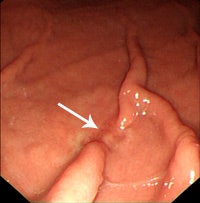

Research from South Korea, published by European Radiology on 1 October in an online first article, has confirmed that when 64-slice systems are used, the technique produces good diagnostic results for determining the depth of mural invasion in patients with gastric cancer. It can be particularly helpful for detecting early gastric cancer, and 64-slice CT is also useful for determining the T staging of gastric cancer, the researchers stated.

"As compared to conventional CT, the ability of multidetector CT to produce multiplanar reformatted images and 3D images, such as virtual gastroscopy, has been shown to improve the diagnostic accuracy of the detection and staging of gastric cancer, and especially early gastric cancer," noted Dr. Jin Woong Kim, Dr. Sang Soo Shin, and their co-authors from the department of radiology at Chonnam National University Hospital in Gwangju.

Overall, gastric cancer was identified in 123 (96.9%) of the 127 cancers on the CT images. Four undetectable cancers on CT were pathologically staged as T1a (n = 3) and T1b (n = 1), respectively. In cases of early gastric cancer (EGC), 56 (73.7%) of the 76 cancers were visible on both the 2D and the 3D images, whereas EGC was identified only on the 2D and the 3D images in two (2.6%) and 14 (18.4%) cancers, respectively.